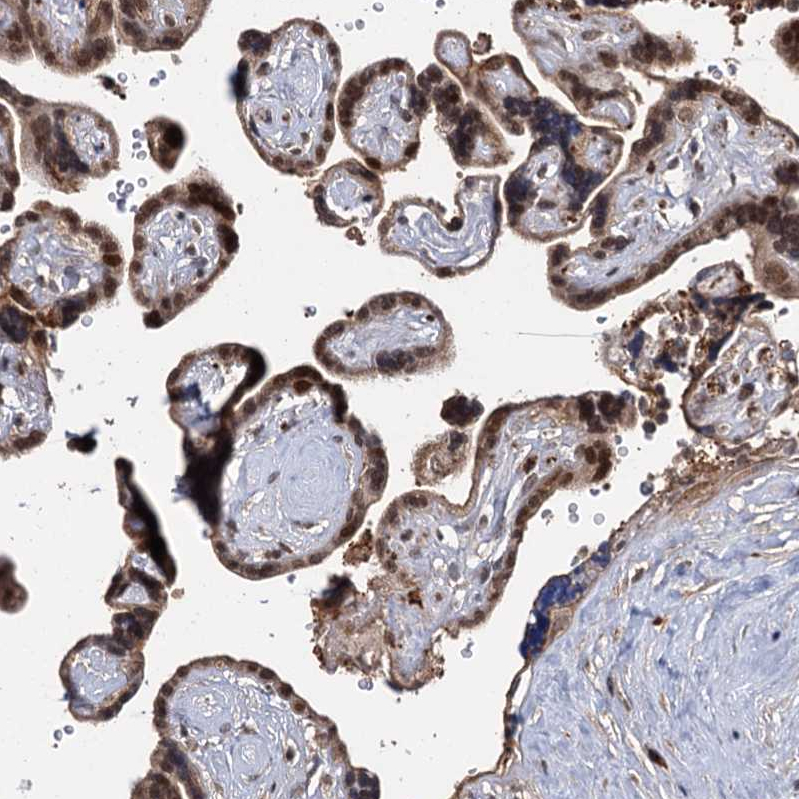

Immunohistochemical staining of human testis shows moderate nuclear positivity in cells in seminiferous ducts.